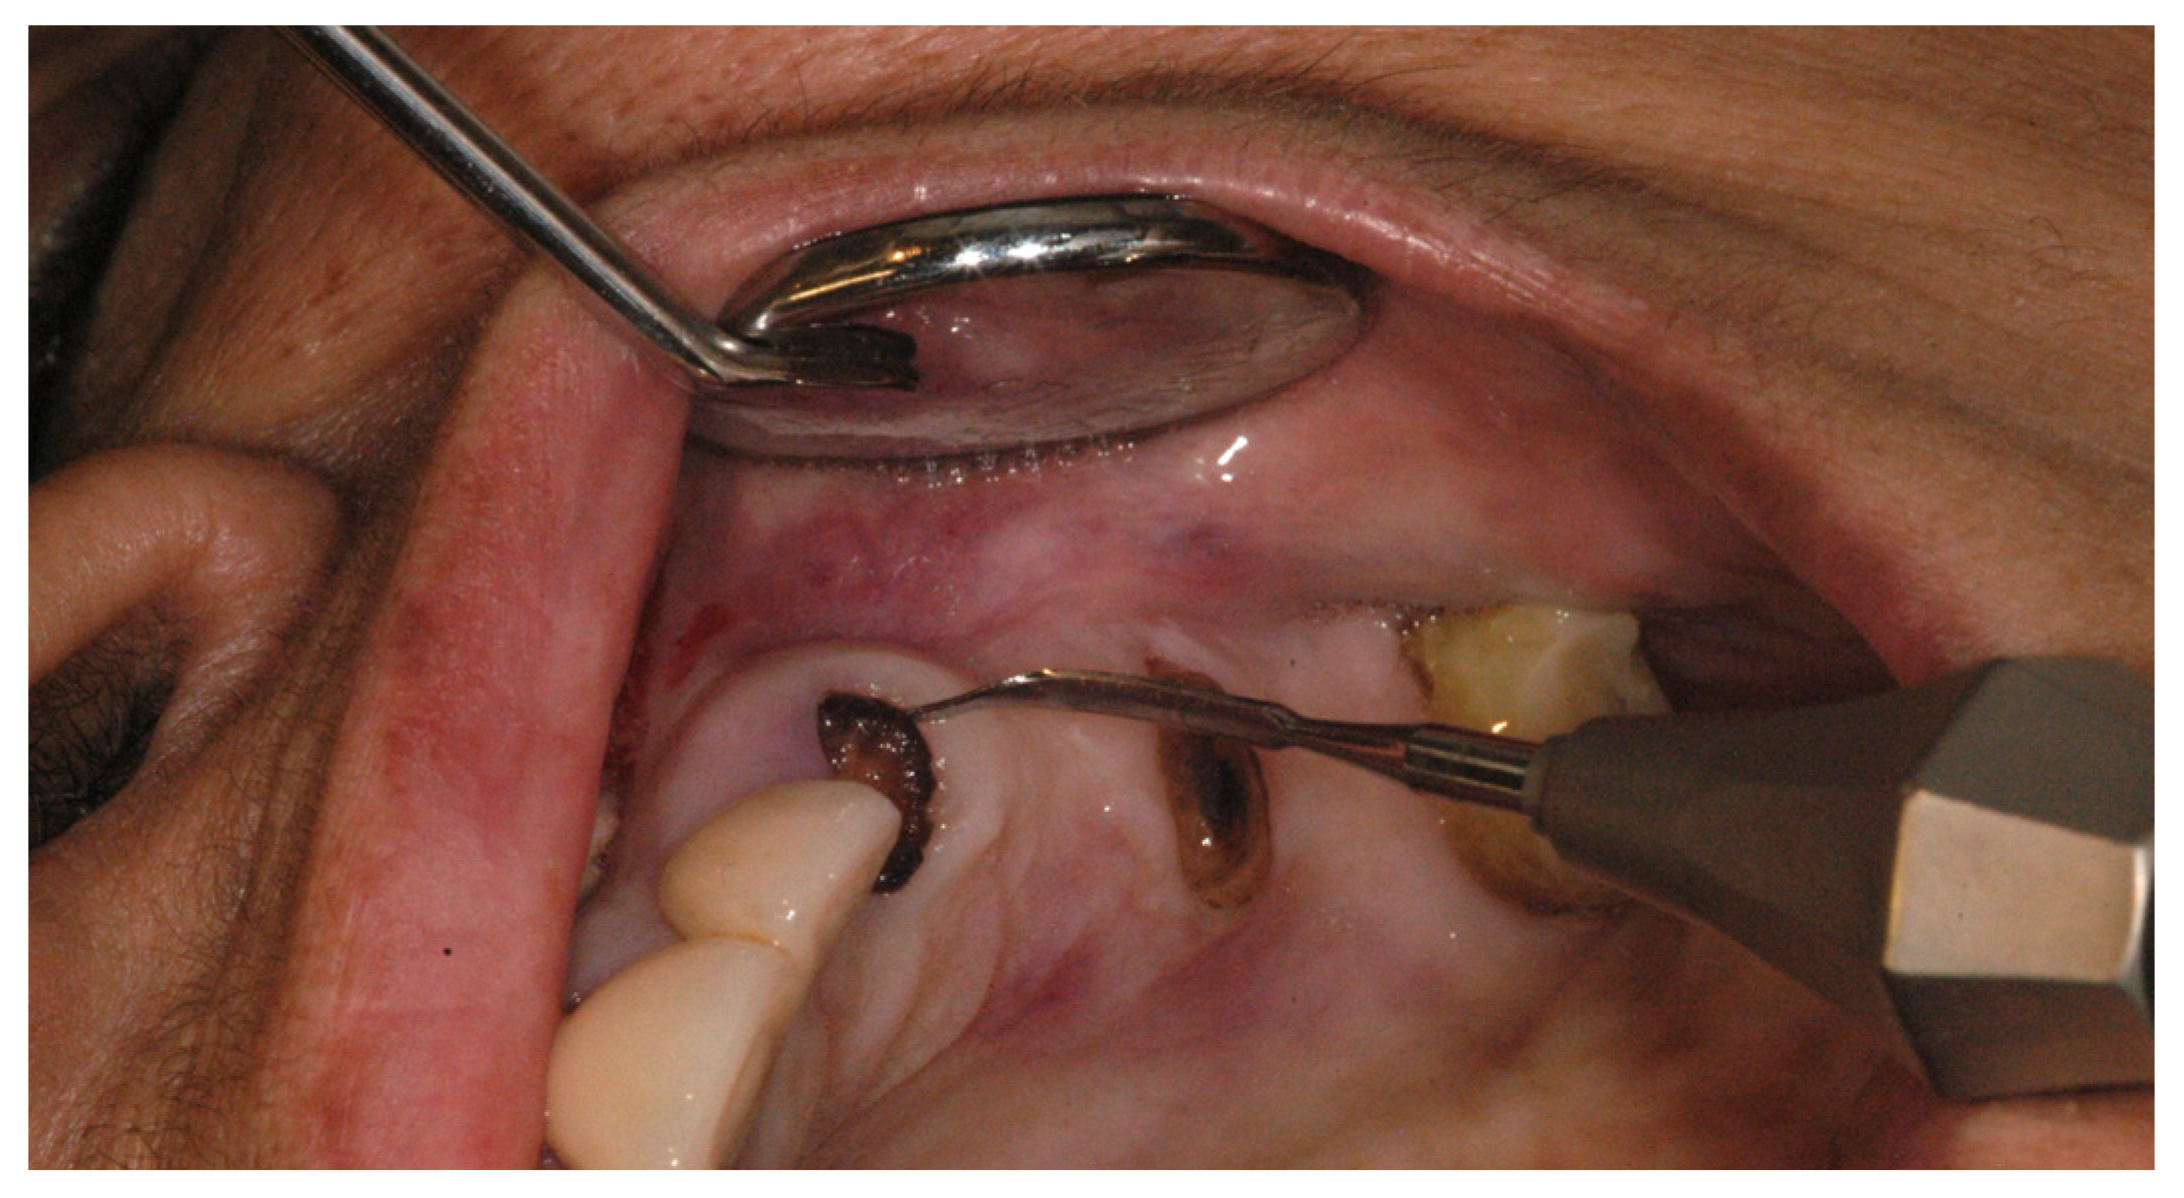

2.2. Case Study

| Step 2 | Extract using minimally invasive technique and clean and irrigate the extraction socket

|

| Step 3 | Augment and suture